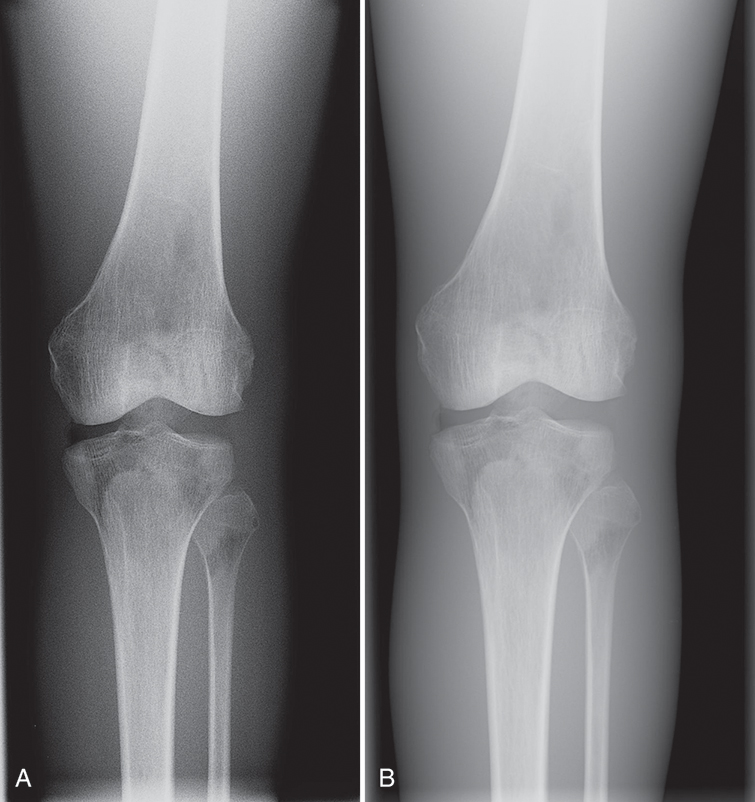

The amount of detail present in any image is known as its spatial resolution. Just as the crystal size and thickness of the phosphor layer determine resolution in film/screen radiography, phosphor layer thickness and pixel size help determine resolution in PSP. The thinner the phosphor layer, the higher the resolution. In film/screen radiography, resolution at its best is limited to approximately 10 line pairs (lp) per millimeter (mm). In general projection radiography PSP imaging, resolution is approximately 2.55 to 5 lp/mm, resulting in less detail. Resolution detail is also affected by the laser beam spot size (the smaller the diameter of the laser beam, the higher the spatial resolution), translation speed (slower speed allows more exposure to be detected), sampling frequency (the higher the sampling frequency, the more exposure detected), and the laser beam sweep in point beam readers (the tighter the sweep or the better shaping of the beam, the higher the resolution). However, because the bit depth, or the number of available shades of gray that can be displayed, is much higher, the difference in resolution is more difficult to discern. More tissue densities on the digital radiograph are seen, giving the appearance of more detail. For example, the fat pads on a lateral elbow are difficult to discern on a film image (Fig. 4.14A). Fat pads are a very important sign for the radiologists to see in pediatric elbow fractures. In the digital image, the fat pads are easily seen (see Fig. 4.14B). This is because of the ability to display more shades of gray, thereby making it possible to visualize more tissues of varying densities; this does not, however, mean that the digital image contains additional detail.

Depending on the type of system being used, the technologist will choose the body part imaged either prior to exposure of the image receptor or after exposure. If the examination room has a PSP housed in the detector in the table or a wall stand, the patient worklist will most likely be in the room’s workstation, which means the technologist may choose the appropriate body part automatically. Always check to make sure the appropriate part has been selected. When using a cassette-based system, the selection of the body part is usually done after exposure and it is imperative that cassettes are kept apart so that the technologist knows which cassette goes with which body part. For example, if a skull examination is to be performed, the technologist would choose “skull” from the workstation menu (Fig. 4.16). Selecting the proper body part and position is important for the proper conversion to take place. Image recognition is accomplished through complex mathematical computer algorithms, and if the improper part and/or position is designated, the image may be processed incorrectly and fail to display properly. For example, if a knee examination is to be performed and the examination selected is for skull, the computer will interpret the exposure for the skull, resulting in improper image display (Fig. 4.17). The resultant image might appear too dark or too light and it might appear grainy or as if it was underexposed. It is not acceptable to select a body part or position other than that being performed simply because it provides a better image. If the proper examination/part selection results in a suboptimal image, then service personnel should be notified of the problem so it can be corrected as soon as possible. Improper menu selections may lead to overexposure of the patient and/or repeated exposure.